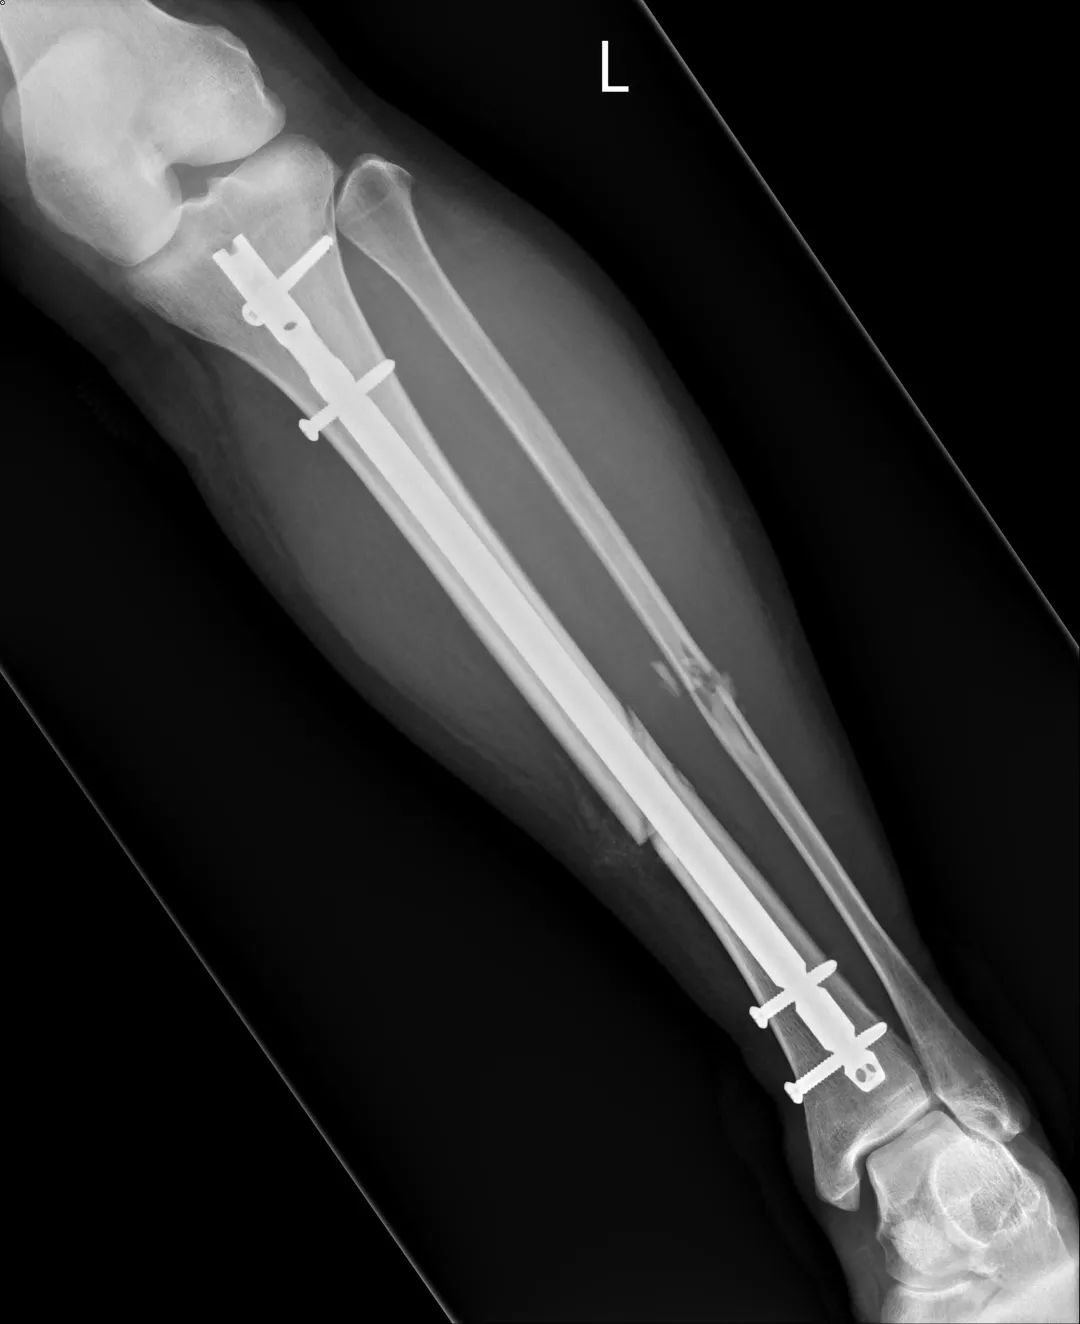

“这是骨折变形了。”

医生告知诊断:小腿里两根骨头都断了,要用手术固定。小腿里有两根骨头,胫骨和腓骨。他们的排列像吃鸡翅时,掰开的那大小骨头。

医生解释手术流程与费用。骨钉有两选择,健保和自费。健保的是不锈钢材质,自费的是钛合金。通常自费医材可拥有较良好的治疗效果。我立即决定用自费医材,商业保险这时候派上用场了。

姐姐国中同学刚好是骨科住院医生,特地过来关心,耐心地说明目前伤势,除了已知的小腿骨折外,他指着脚背说,这里也有骨折。

我马上说出骨头学名:跖骨,因为同一双脚第四根有断过。

复健科医生看到X光片后都说:“你这个很严重耶。”为了想尽快恢复生活,我积极去复健治疗。因长时间卧床,受伤腿肌肉严重萎缩,努力运动,抵挡肌肉流失的速度。